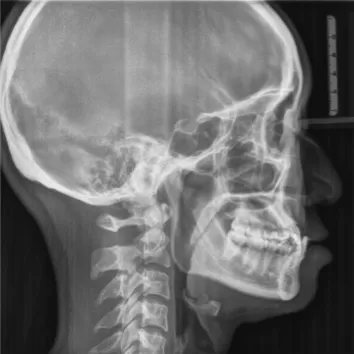

X-rays before treatment

[Panoramic Radiography/Lateral Cephalogram]